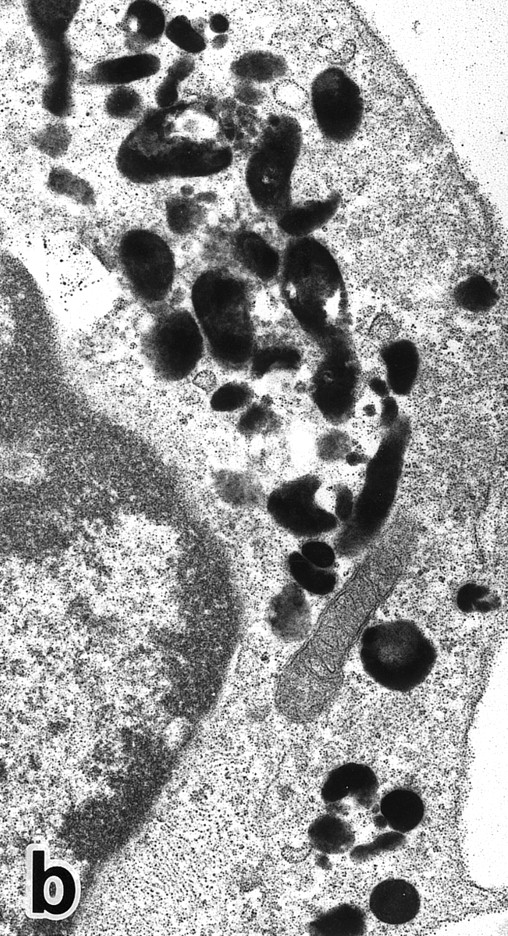

Representative appearance of a portion of a PMN that appeared in a culture of nonleukemic bone marrow mononuclear cells incubated in the presence of ATRA for 1 week. Both MPO-positive and -negative (arrow) cytoplasmic granules are present, with the former outnumbering the latter. Large spherical lipid droplets (L) are also present. N, nucleus. (MPO-stained section, original magnification × 17,700.)